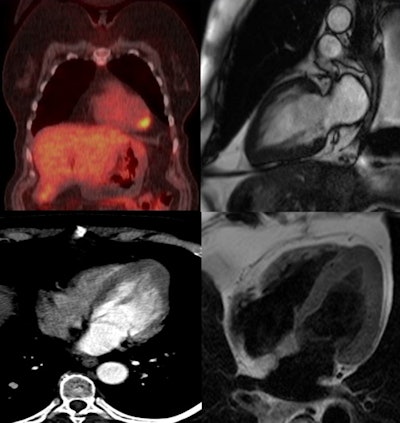

At the Milan meeting, Gezmis reported about the case of a lung cancer patient with focal cardiac FDG uptake on whole-body oncological PET/CT, which turned out to reflect apical HCM when further evaluated with CMR.

A subsequent whole-body FDG-PET/CT scan showed uptake in the mass and right hilar lymph node, confirming the diagnosis, but increased focal activity was also noted at the apex of the left ventricle, which appeared to be within the wall rather than the lumen. This raised the possibility of cardiac metastasis, which would have changed the management of the patient, and further evaluation was required.

Despite the fact it was not ECG-gated, the thoracic CT scan was reassessed regarding the heart by putting the images into true cardiac planes using multiplanar reconstruction. This demonstrated the loss of tapering of myocardium from the base to the apex with thickening of distal walls, suggesting apical HCM.

Contrast-enhanced cardiac MRI was performed to rule out metastasis and validate the apical HCM diagnosis. The images showed disproportionate and focal wall thickening in the left ventricular apex, which corresponded with the area of avidity on the PET/CT scan. There was also a "spade-like" configuration of the apical left ventricular cavity, and contractility of myocardium was preserved.

"No mass or gadolinium enhancement was noted and the appearance was in keeping with an apical hypertrophic cardiomyopathy phenotype. The pathology test results from the CT-guided biopsy of the lung mass and subsequently performed right lower lobectomy were adenocarcinoma. The benefit of chemotherapy was outweighed by risk and the patient has been under follow-up since then," Gezmis concluded.